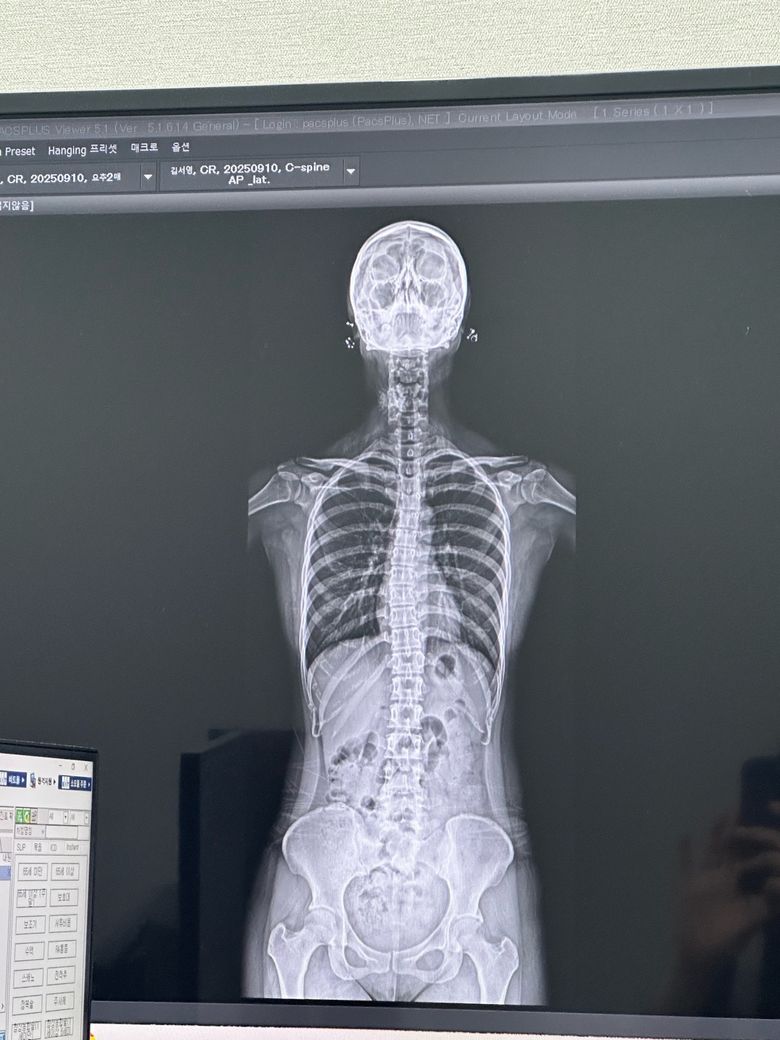

도수치료 안해도되나요? 디스크인지도 봐주세요

집에서 운동하면 휜 허리나 거북목이 다시 돌아올수 있을까요?? 집에서 허리운동해도될까요? 그리고 제가 허리디스크인지도 궁금합니다 까먹고 못물어봤어요 디스크사이에 공간이 있어야하는데 줄어들어잇다 하더라고요

• 1번 째 사진

X-ray상으로 디스크를 정확하게 알 수는 없으며 척추체 사이가 간격이 좁아져 있다면 디스크 이상을 의심해볼 수 있습니다.

X-ray상 골반틀어짐, 척추측만증 등 전체적으로 신체 균형이 틀어져 있는 것으로 보이며 잘 못된 운동은 증상을 더 악화시킬 수 있기때문에 정형외과에서 진료받으시고 체형교정을 위한 도수치료를 받으시는 것이 도움이 되실 것입니다.